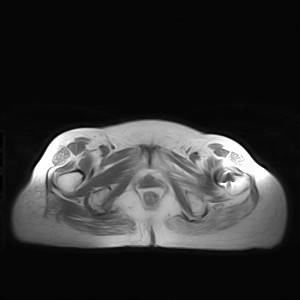

图像太差了 1、右侧臀肌旁脓肿? 建议增强 2、左侧股骨头坏死并半脱位

1、左侧股骨头坏死并髋关节半脱位;

2、右侧臀肌感染,(可能褥疮所致)